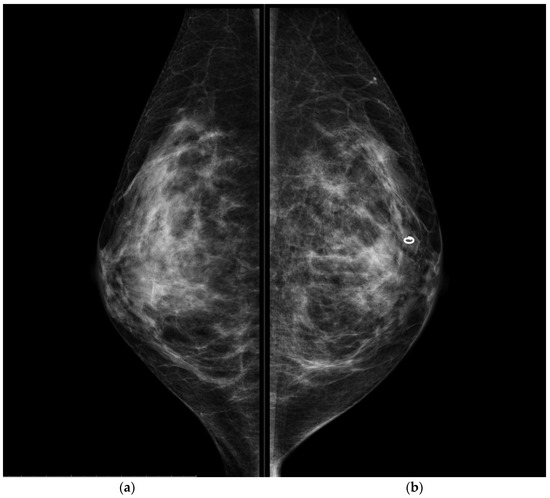

CESM also confirmed the presence of a metallic marker in the left retro-areolar breast, previously released in the breast biopsy site (Figure 1, Figure 2, Figure 3 and Figure 4).

Figure 3. Conventional MLO projections of the right breast (a) and left breast (b). The circular-shape marker released after US-guided biopsy was present in the retro-areolar left breast. MLO projections, as CC, showed no mammographic alterations.